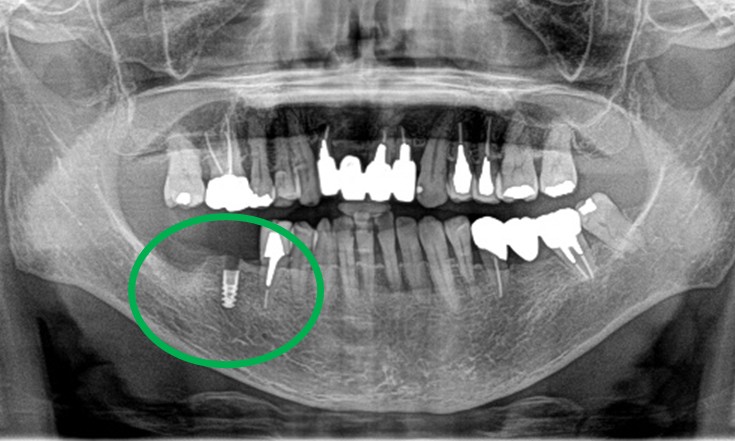

男性 Nさん 70代 (インプラント)

主訴

右下奥の歯が、グラグラして噛むと痛い。

治療内容

歯根の周りの骨が全く無い状態でしたので、保存することができず抜歯しました。3本歯がないところに2本インプラントを埋入しました。

所感

抜歯後、歯がなくなったところを補う方法には、部分入れ歯とインプラントがあります。この症例の場合、右下以外ほとんど歯が残っていますので、もし部分入れ歯にした場合、入れ歯のところで他のところと同じ感覚で噛むことができないので、慣れることが大変です。また部分入れ歯の支えになっている歯に負担がかかりますので、今後さらに歯を失う可能性が大きくなります。インプラントは、自分の歯と同じ感覚で噛むことができ、単独で植立していますので他の歯に負担がかかることがありませんので、更に歯を失うことを防ぎます。

インプラント2本:¥363,000×2本=¥726,000(税込)

ポンティック1本:¥115,500(税込)

合計:¥841,500(税込)

Before

※赤丸を抜歯しました。

After